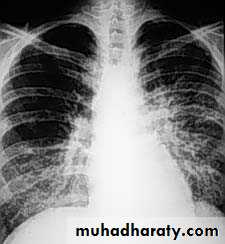

PNEUMONIA

Community-acquired pneumonia (CAP) :acute infection of the pulmonary parenchyma in a patient who has acquired the infection in the community, as distinguished from….hospital-acquired pneumonia (nosocomial).

Viral pneumonia

Most children younger than 5 years of age who are admitted to the hospital with pneumonia have viral pneumonia .Viral pneumonia does not require antibiotic therapy, unless a mixed infection or secondary bacterial infection is suspected.

Typical bacterial pneumonia

Typical bacterial pneumonia may occur in children of all ages.Streptococcus pneumoniae is the most common type of bacterial cause of pneumonia in children of all ages.